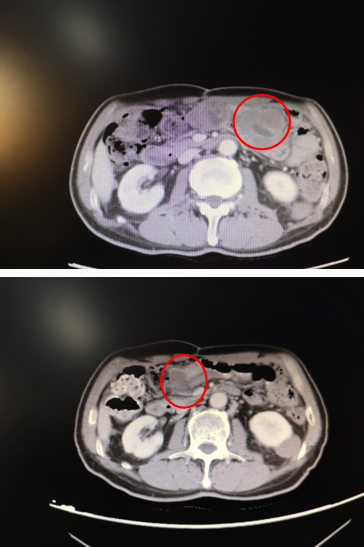

2011-10-10复查腹部CT示:左下腹不规则软组织团块影,病灶向右下方延伸,右下腹前壁亦见软组织结节影,提示腹腔占位,考虑肠道间质瘤复发。

2016年3月复查CT:肝转移,腹盆腔多发转移灶。

2018年11月复查CT:肝、腹腔转移灶较前明显增大。

2019.03复查CT:肝脏、腹腔肿块缩小。